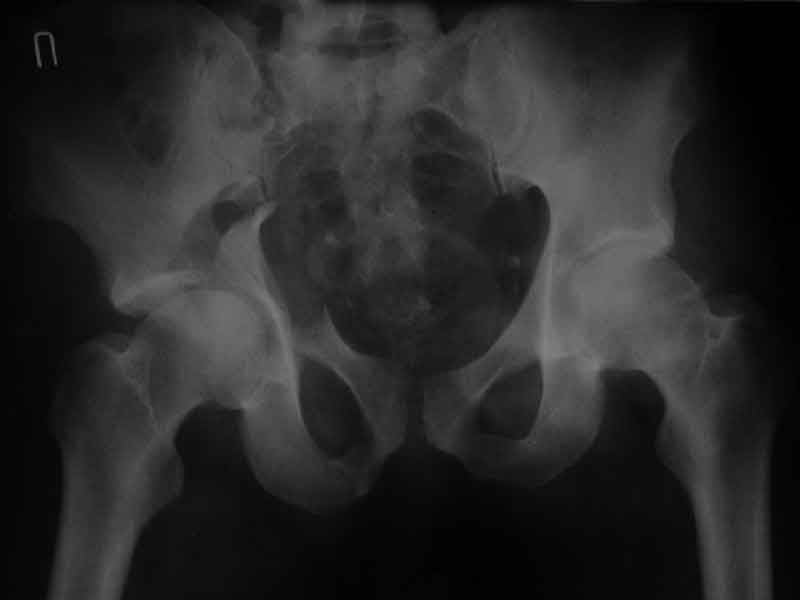

Дополнение, минимальный набор необходимых прекций, необходимых для лечения повреждений вертлужной впадины

Фас. Inlet